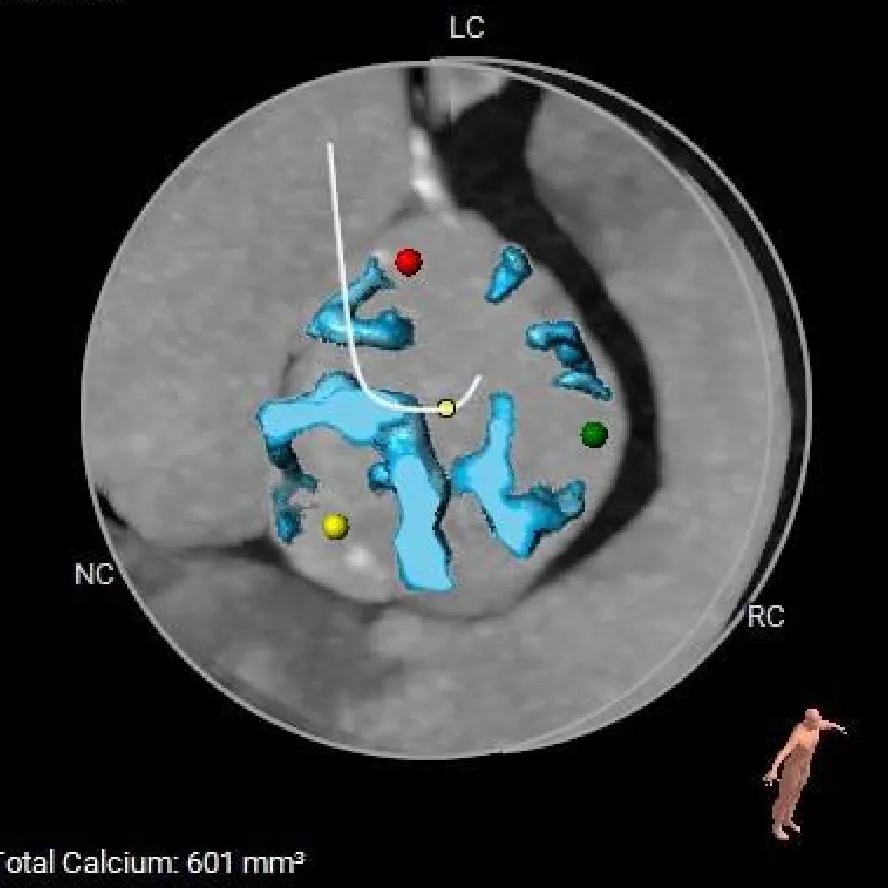

钙化积分

601mm3

VR图